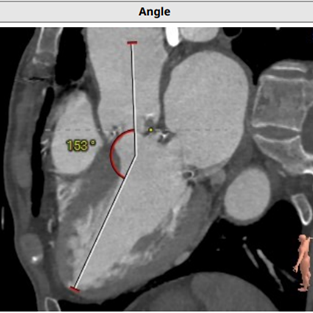

投照角度(LAO 14,CRA 1)、左室二尖瓣轴线角度(121度)和入路角度(153度):